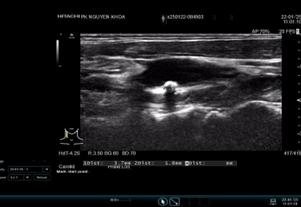

Hình ảnh siêu âm thực hiện tại phòng khám đa khoa Nguyên Khoa

Hình 1.Hình ảnh siêu âm B-mode động mạch mạch cảnh chung bên trái ghi nhận mảng vôi hoá kt # 3.7 * 1.8mm tại hành cảnh, phổ doppler chưa ghi nhận bất thường.

Hình 2. Hình ảnh siêu âm doppler màu cho thấy động mạch đốt sống đảo chiều hoàn toàn so với động mạch cảnh cùng bên.

Hình 3. Hình ảnh siêu âm duplex cho thấy phổ doppler xung của động mạch đốt sống bên trái 1 pha, đảo ngược hoàn toàn thì tâm thu PSV# 49cm/s.